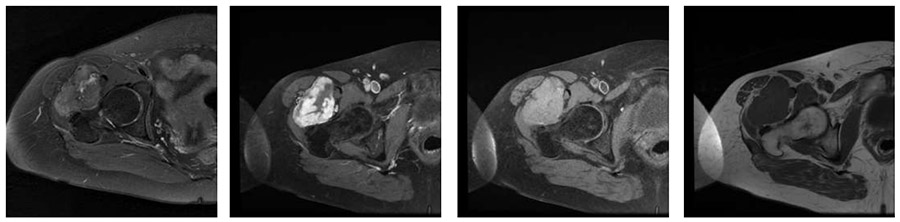

Ameliyat Öncesi: MR’da sağ kalça eklemi anterior yerleşimli düzensiz sınırlı heterojen yumuşak doku kitlesi görülmekte